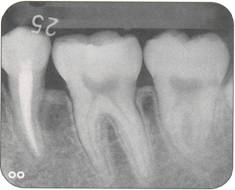

Fi 545e45f g 5-1d Preoperative periapical radiograph. |

Fi 545e45f g 5-1f After extraction offirst molar from the recipient site. Fi 545e45f g 5-1 g The donor tooth. Note the adequate root form and amount of periodontal ligament on the root. Fi 545e45f g 5-1 h Measurement of the mesiodistal width of the donor tooth. |

Fi 545e45f g 5-1 i Measurement of the mesiodistal width of the recipient site. If the mesiodistal width of the donor tooth is greater than that of the recipient site, the proximal walls of the adjacent teeth are reduced to fit the donor tooth. Fi 545e45f g 5-1j Preparation of the recipient site. Removal of alveolar septum is done with a minirongeur. Fi 545e45f g 5-1 k After removal of the alveolar septum. |

Fi 545e45f g 5-11 Preparation of the recipient site with surgical round burs. Fi 545e45f g 5-1 m Prepared recipient site and extraction site of the donor tooth. Fi 545e45f g 5-1 n After transplantation of the donor tooth and suturing of the flap. |

Fi 545e45f g 5-10 Stabilization of the donor tooth. The donor tooth has been splinted to the adjacent tooth with twisted wire and selfcured composite resin after etching and bonding. Fi 545e45f g 5-1 p After transplantation. |

Fi 545e45f g 5-15 Three weeks after transplantation. Root canal therapy was started 2 weeks after transplantation. After temporary obturation with calcium hydroxide, the root canal was obturated with gutta percha in 5 weeks. Fi 545e45f g 5-1t Two and one half months after transplantation. |

Fi 545e45f g 5-1 u Definitive occlusal restoration of the donor tooth with composite resin. Fi 545e45f g 5-1v One year 3 months after transplantation. Normal periodontal ligament space and lamina dura are observed. |